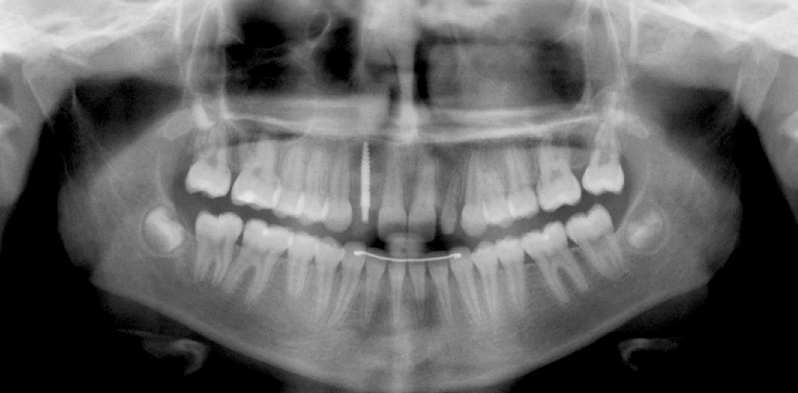

Fig 3. Implants were placed in a 20-year-old female patient in the Nos. 7 and 11 sites with a pontic replacing No. 10.

Figure 3

Fig 4. A 15-year postoperative photograph of the patient in Fig 3 illustrates the significant infraocclusion of the implants compared to the natural teeth. Also, note the blue tissue discoloration over implants Nos. 7 and 11.

Figure 4

A third risk of using an implant to replace a missing lateral incisor is the continued vertical growth of the alveolar bone and eruption of the teeth adjacent to the implant.9,10 Traditionally, it has been taught that an implant can be safely placed when alveolar bone growth is confirmed complete with serial radiographs. However, numerous studies call that rule into question.11-16 Bernard et al evaluated vertical changes in teeth adjacent to implants in a young group of patients (15.5 to 21 years) and in a mature group (40 to 55 years), over a mean time of 4.2 years.17 In the young group, infraocclusion of the implant crowns ranged from 0.1 mm to 1.65 mm, while in the mature group the infraocclusion of the implant crowns ranged from 0.12 mm to 1.86 mm. An example of infraocclusion that occurred in a young implant patient over time is depicted in Figure 3 and Figure 4. Based on classic literature as cited here, it seems prudent to delay the placement of implants in high-risk areas, such as the maxillary lateral incisor region, for as long as possible or perhaps avoid it altogether.